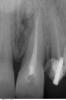

Мaxim Опубликовано 27 апреля, 2013 Поделиться Опубликовано 27 апреля, 2013 Уважаемые коллеги, подскажите как бы кто поступил в данной ситуации:21 наружняя резорбция, в канале цемент, при попытке ревизии выскочили в резорбцию, инструмент заклинил и остался. В канале Vitapex, последние 2 мм не пройдены.У нас варианта 2:1.Пломбировка альфа-гуттой, хирургическим путем извлечь инструмент, MTA, остеопластический материал и под наблюдение.2..Пломбировка альфа-гуттой, резекция,MTA, остеопластический материал и под наблюдение.Снимки. Прикрепленные изображения Ссылка на комментарий